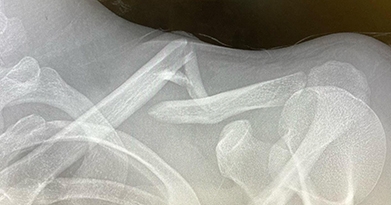

He has extensive experience in the care of patients with shoulder, elbow and knee injuries. Furthermore, he has taken care of athletes at all levels—from the weekend warrior to the professional athlete. Dr. Momaya currently serves as team physician for UAB Athletics, Birmingham Legion FC, Birmingham Stallions, Bulls Hockey, BUSA soccer, Hoover-Vestavia Soccer, and multiple high schools. In addition, Dr. Momaya is an active clinician scientist. His research has been published in leading Orthopedic journals and presented at multiple local and national meetings.